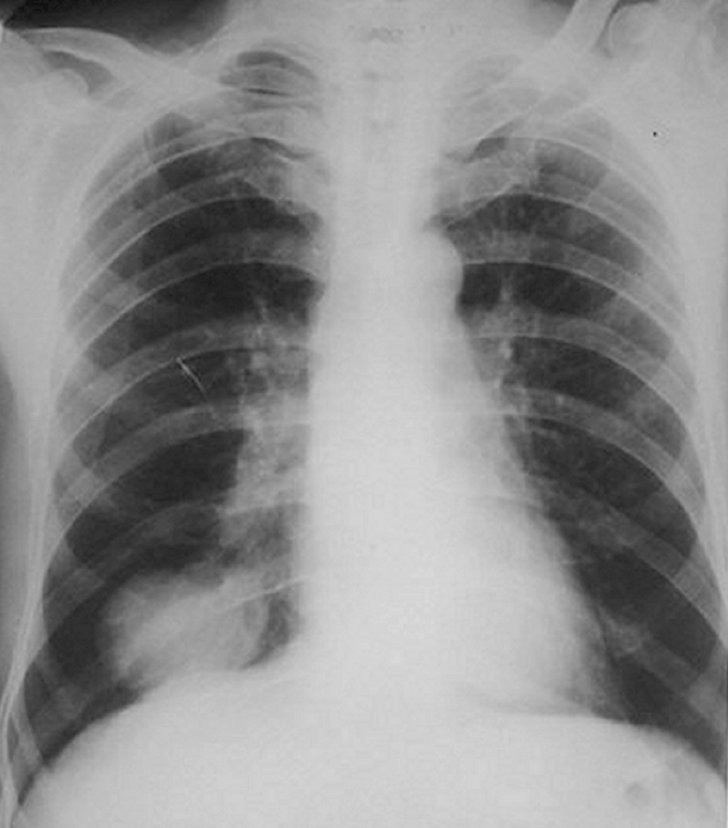

Carcinom bronho-pulmonar central

Neoplasm pulmonar central